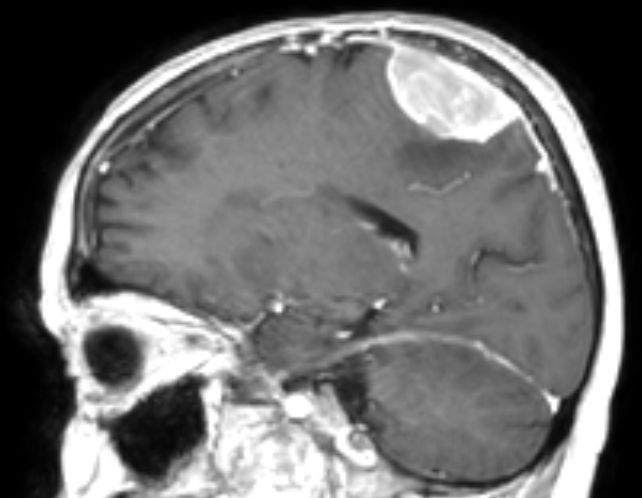

| Meningeom frontal |

59-jähriger Patient, der wegen AV-Block in die Kardiologie eingeliefert wurde. Das CT zeigt einen hirninvasiven Tumor, der die Mittellinie überschreitet. Postoperativ ergab sich ein Meningeom 2. Grades. | . |